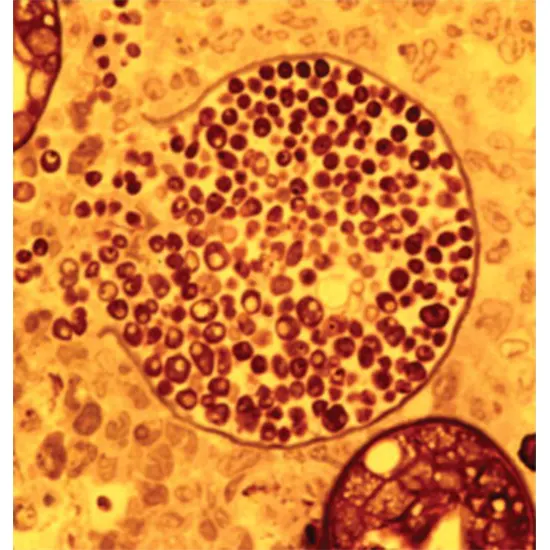

Trypomastigotes develop into the intracellular amastigote form in the cytoplasm, and this form then replicates with a doubling time of roughly 12 hours over the course of 4 to 5 days. At the conclusion of this time, the host cell ruptures, the amastigotes change into trypomastigotes, and the trypomastigotes are released into the circulation. The circulating parasites are then able to enter fresh cells, start fresh replication cycles, and infect vectors that feed on the host. The infection lasts the entire lifetime of the mammalian host if antitrypanosomal therapy is unsuccessful.